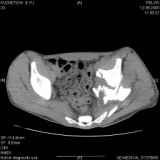

Уважаемые коллеги! Хотелось бы услышать совет по тактике лечения представлленого больного.Поступил после лечения в одном изотделений области. Травма 2,5 месяца назад. После выведенияиз шока был произведен остеосинтез перелома бедра, предплечья, до перевода к нам проводилосьвытяжение по оси шейки бедра за стержень, введенный в большой вертел. На сегодня деформацияригидна, клинически мобильности не определяется. Заранее признателен. P.S. Данный вид травм не включен в перечень "высокотехнологичных операций", направить длялечения по квотам Минздрава очень сложно.

Это обзорные и косые снимки

Привет, Леонид. Оскольчатый высокий двухколонный перелом в такие сроки трогать не надо, т.к. это про такие переломы сказано: "кто с ножом на Ж. пойдет тот в ней и останется...".